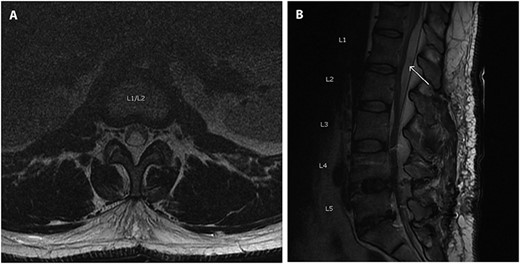

A 34-year-old male who was admitted for revision L5-S1 and primary L4-L5 decompression and posterolateral instrumented fusion of L4-S1. Eight months prior he had undergone a left sided laminectomy and discectomy of L5-S1 for disk herniation. A few months after his initial fusion procedure, the patient reported falling down a flight of stairs and developed worsening lower extremity pain and radicular symptom. Preoperative imaging 3 months prior to his revision showed recurrent disk herniation at L5-S1 as well as new herniation at L4-L5 (Fig. 1). The procedure went without complication, with no note of durotomy, and the fascia was closed using a bidirectional barbed suture.

Axial (A) and Sagittal (B) T2 MRI imaging obtained preoperatively when presented for back pain, 8-months after a previous L5-S1 laminectomy/diseconomy. Images here show no evidence of pre-operative subdural fluid collection.